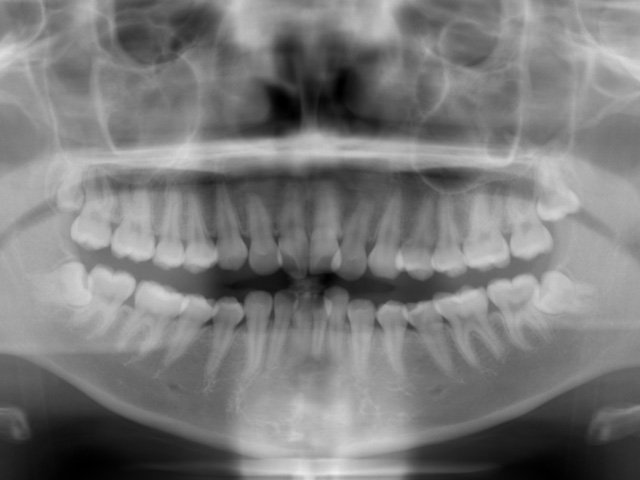

パントモレントゲンの画像です。

上下左右の親知らずが4歯とも埋伏しています。これらを抜歯してこのスペースを利用して叢生と出っ歯を改善できそうです。